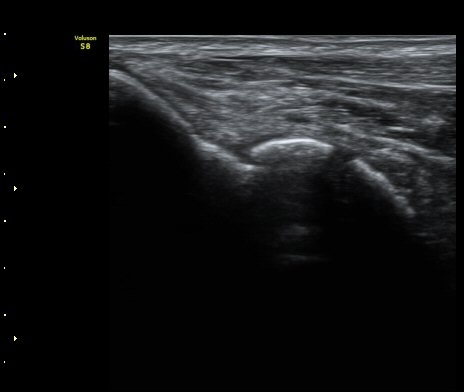

[ÆÈ²ÞÄ¡] ÆÈ²ÞÄ¡ °üÀý³» À¯¸®Ã¼¿¡ ÀÇÇÑ ÆÈ²ÞÄ¡ ÅðÇ༺ °üÀý¿°

³²ÀÚ/ 44¼¼

ÁÖÁõ»ó

ÆÈ±ÀÄ¡ ÅëÁõ

ÃÊÀ½ÆÄ °Ë»ç